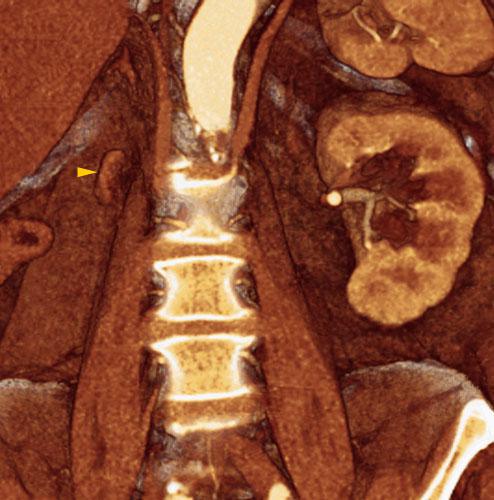

Riñón único pélvico